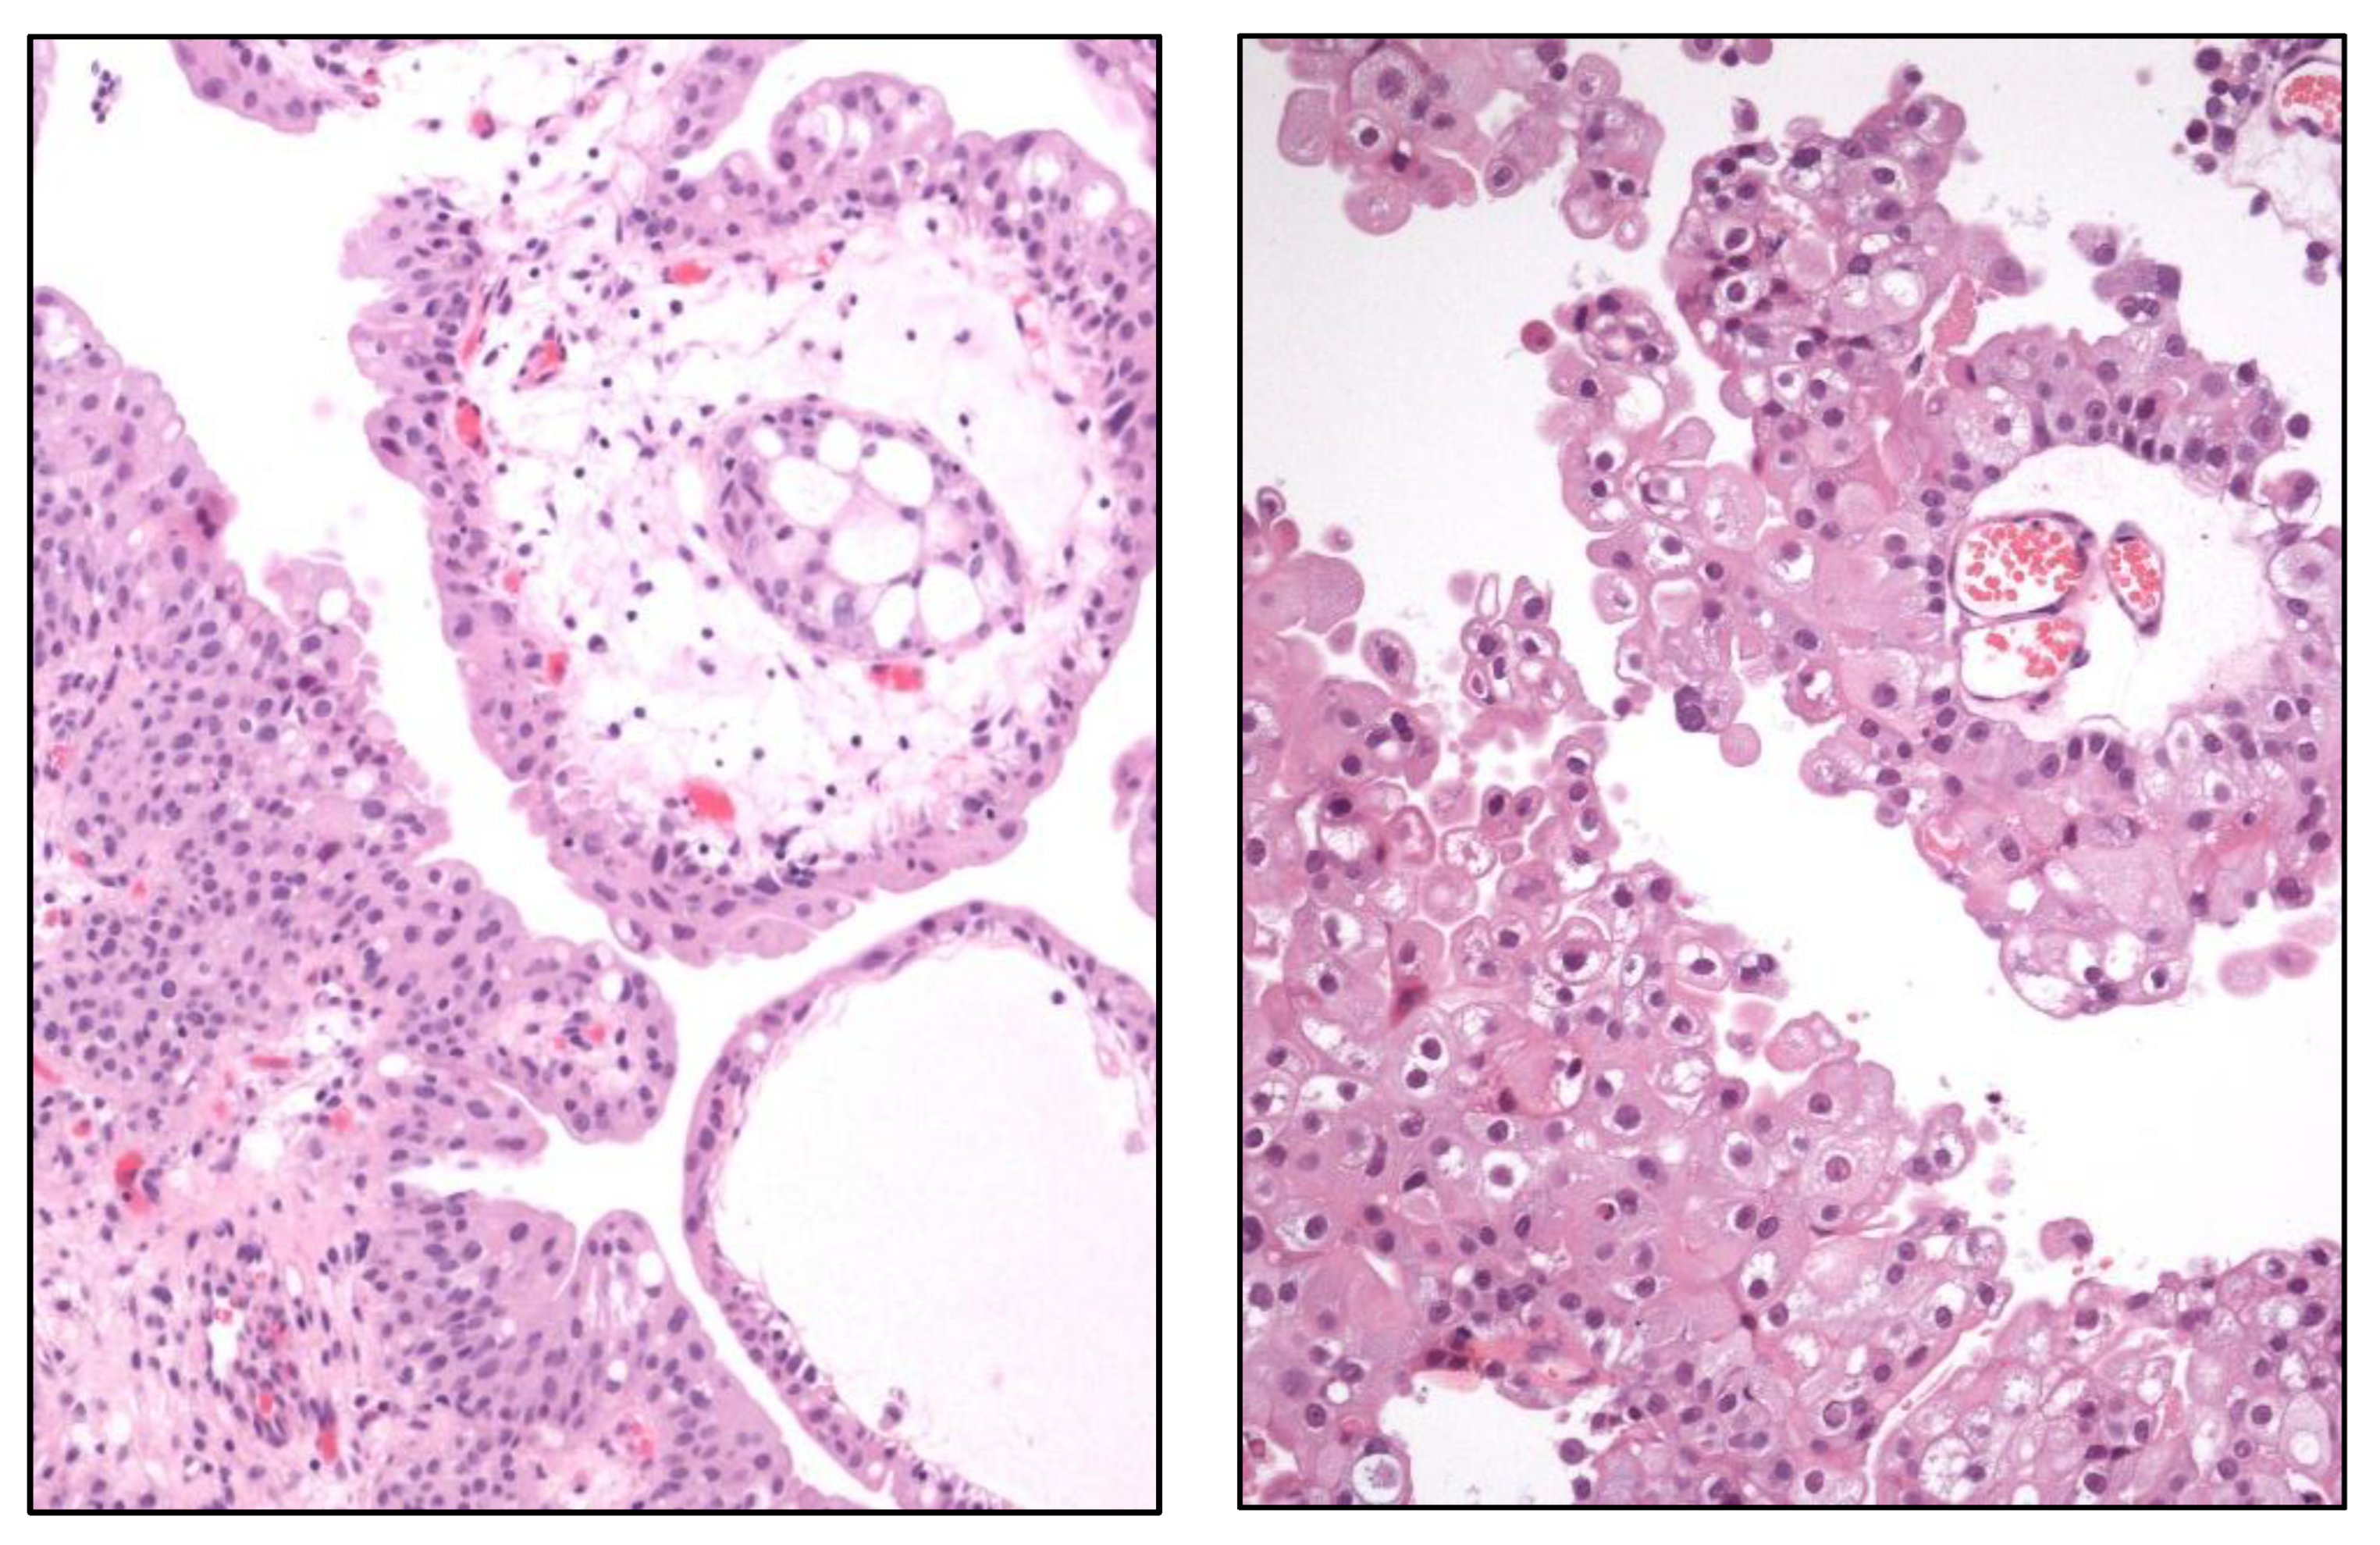

Large “nested” UC (Figure 3)

Clear cell UC is renamed as “glycogen-rich” clear cell UC (Figure 3) to distinguish it from the adenocarcinoma of Müllerian-type.

Glandular, squamous, trophoblastic (Figure 3), Müllerian, and neuroendocrine morphologies must be specifically mentioned in the pathological report of UC, including its approximate percentage.

Micropapillary, plasmacytoid (Figure 3), and other “wolves in lamb clothes” must be recognized and specifically reported, either pure or mixed, in the pathological report of UC.

Figure 3. Histologic images of a clear cell (upper left), large nested (upper right), trophoblastic differentiation (lower left), and plasmacytoid (lower right) urothelial carcinoma of the urinary bladder.